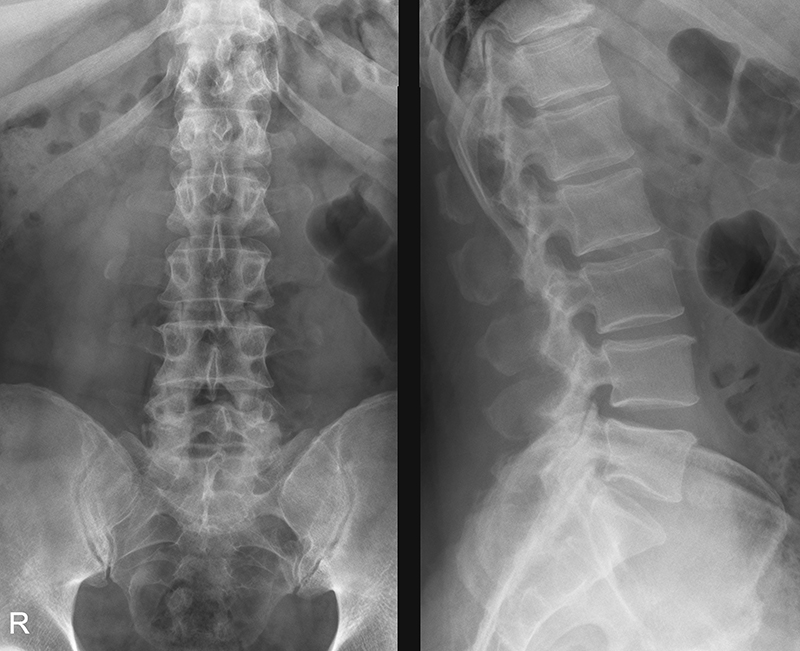

Для исследования поясницы предпочтителен функциональный рентген. Снимки выполняются в боковой проекции, когда пациент находится в лежачем положении с максимальным разгибанием. Более информативной будет рентгенография спины в положении сидя или стоя. Однако технические возможности рентгеновского кабинета не всегда позволяют использовать этот метод.

Чтобы получить полное представление, снимки делают в трех проекциях. Первый снимок выполняется сзади. Второй — сбоку при максимальном сгибании спины. Третий также сбоку, но при максимальном разгибании тела.

При рентгенографии поясничного отдела врач анализирует структуру костной ткани позвонков, оценивает наличие жидкости и выявляет деформации межпозвоночных дисков. Специалист ставит диагнозы, связанные с заболеваниями позвоночника.

Рентгенологическое обследование может выявить следующие патологии: